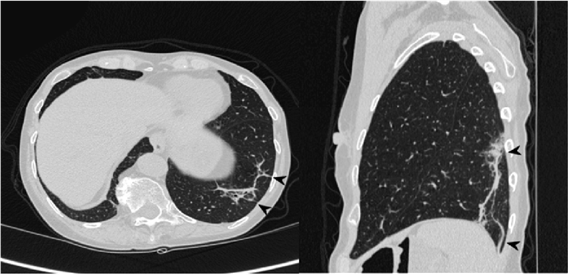

2. 影像学表现

①肺实变磨玻璃密度影;②小叶周围阴影;③环礁征;④结节或肿块;⑤小叶间隔增厚;⑥束状或条带阴影;⑦进行性纤维化。

小叶周围型:

图片

线状和带状影:

进行性纤维化:

3. 影像学特点

(1)典型影像:斑片状肺泡浸润影(典型COP)。

(2)不常见影像:孤立性阴影(局灶性COP);浸润性阴影(浸润性COP)。

(3)少见影像:反晕轮征;进行性肺纤维化并网格及实变;多发性结节;支气管中央型实变;不规则线或带状影;小叶周围型阴影。